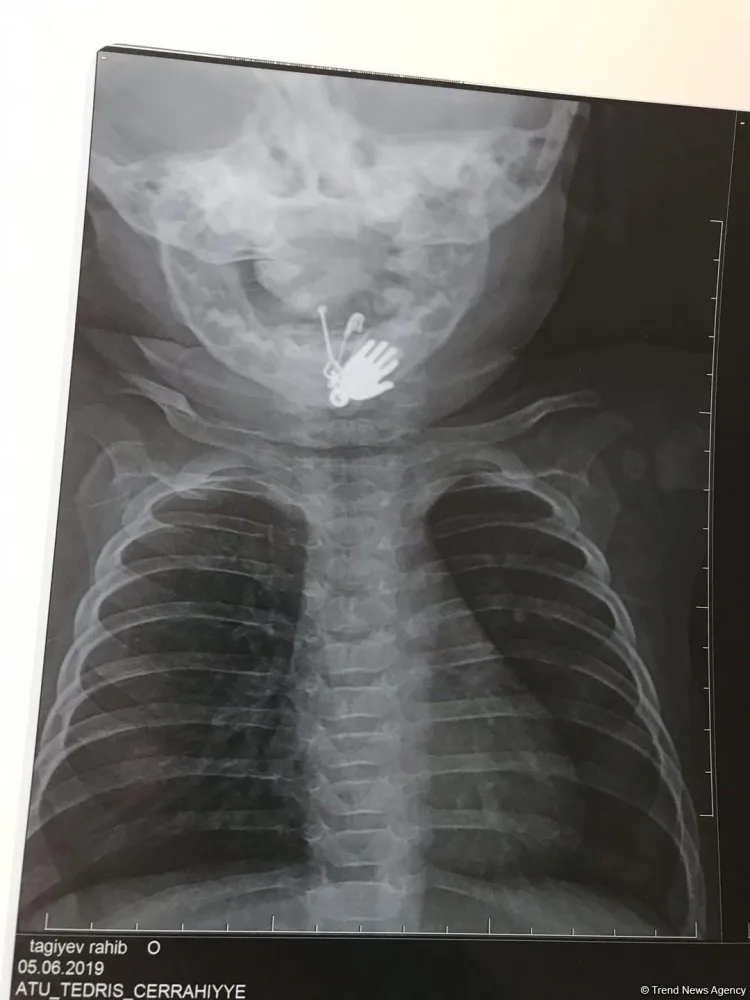

Azərbaycanda altı aylıq körpənin mədəsindən sancaq və digər cisimlər çıxarılıb.

News24.az Trend-ə istinadən xəbər verir ki, hadisə Biləsuvar rayonunda baş verib. Belə ki, sözügedən rayonda valideyn yeni doğulan oğlan uşağına gözdəyməyə qarşı daş və ələmi sancaqla onun paltarına taxıb. Bir müddətdən sonra altı ayrıq körpənin vəziyyəti pisləşib. Uşaqda iştahsızlıq və tənəffüs çatışmazlığı qeydə alınıb.

Valideyn tərəfindən Bakıya xəstəxanaya çatdırılan uşağın mədəsində yad cismin olduğu məlum olub. Belə ki, altı aylıq körpə sancağı və üzərində olan digər əşyaları udub. Ə.F.Qarayev adına 2 saylı uşaq kliniki xəstəxanasında endoskopik üsul ilə körpənin mədəsindən həmin əşyalar çıxarılıb.